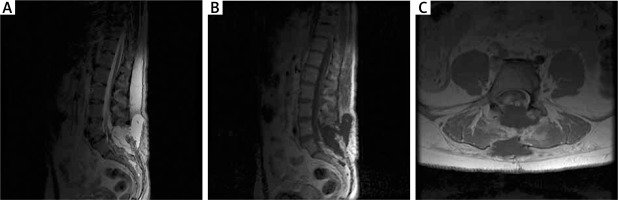

Figure 2

MRI examination in the early postoperative period in the first patient. A – T2-weighted postoperative study with visible fluid cyst. B – T1-weighted contrast-enhanced MR study with visible cyst and partially removed adipoma. C – Axial sections of T2-weighted contrast-enhanced MR study; fluid collection and degree of resection visible